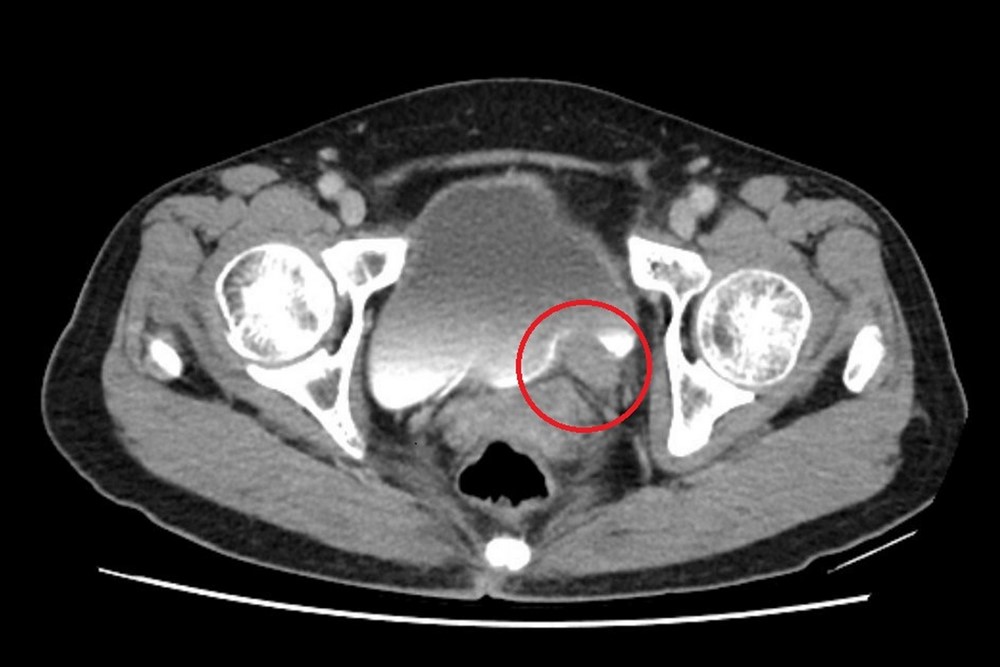

剛取得敬老卡沒幾年的林女士,身體一向硬朗,近期卻發現自己上廁所時尿尿顏色異常,她原本以為只是小問題,至台北慈濟醫院檢查後,竟發現左側輸尿管末端長了一顆五公分的腫瘤,並造成腎水腫。泌尿科許竣凱醫師為林女士確診罹患輸尿管泌尿上皮癌,先安排化療縮小腫瘤,再利用達文西手術切除腫瘤並重建輸尿管,成功保留腎臟功能。林女士術後追蹤至今,病情控制良好。

電腦斷層顯示,病人左側輸尿管末端約五公分大的腫瘤。圖/台北慈院提供